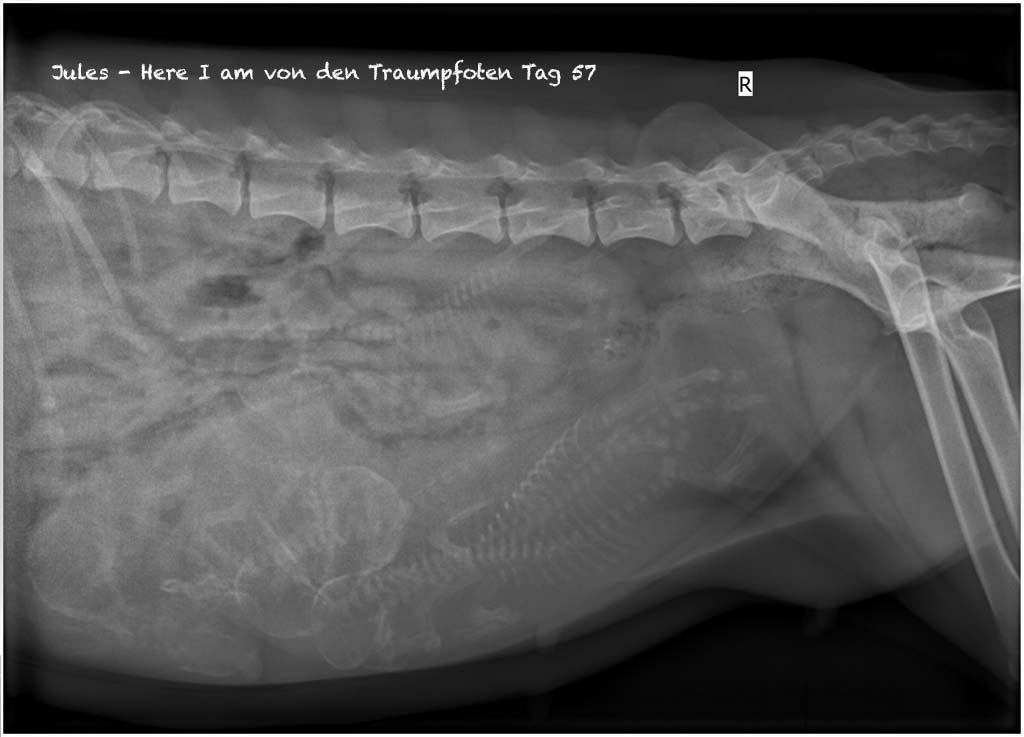

Heute ist bezogen auf den ersten Decktag der 57 Trächtigkeitstag. Jules hat aktuell 5,2 kg Gewichtszunahme und auch deutlich an Bauchumfang zugelegt. Dadurch, dass sie mit ihren 51cm groß und zusätzlich lang ist, verteilen sich die Nachwuchsracker äußerlich recht gleichmäßig. Schaut man wiederum das Röntgenbild an, so ist bereits jetzt Kontaktliegen an der Tagesordnung. Aber noch hat ja jeder seine Privatsphäre in seiner ganz persönlichen 1-Zimmerwohnung.

Jules - Here I am von den Traumpfoten

Trächtigkeitstag 57